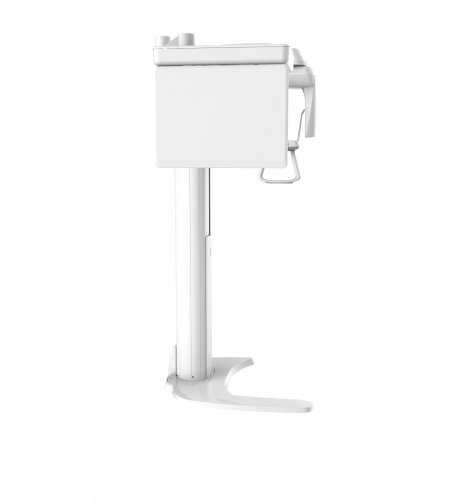

| TYPE | TOP VIEW | FRONT VIEW |

|---|---|---|

|

PaX-i (Pano) |

|

|

|

PaX-i SC (Pano/Scan Ceph) |

|

|